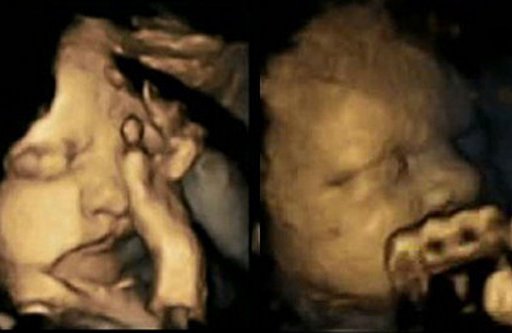

Une médecin britannique est parvenue a démontrer en images la réaction d'un foetus dans le ventre de sa mère lorsque celle-ci est en train de fumer.

Pour sensibiliser les femmes enceintes à l'arrêt de la cigarette pendant la grossesse, le Dr Nadja Reissland a capturé en images la réaction d'un foetus lorsque sa mère fume. Pour cela, elle a étudié les cas de 20 femmes enceintes dont quatre ont déclaré fumer en moyenne 14 cigarettes par jour. Toutes étaient suivies à l'hôpital James Cook University (Royaume-Uni).